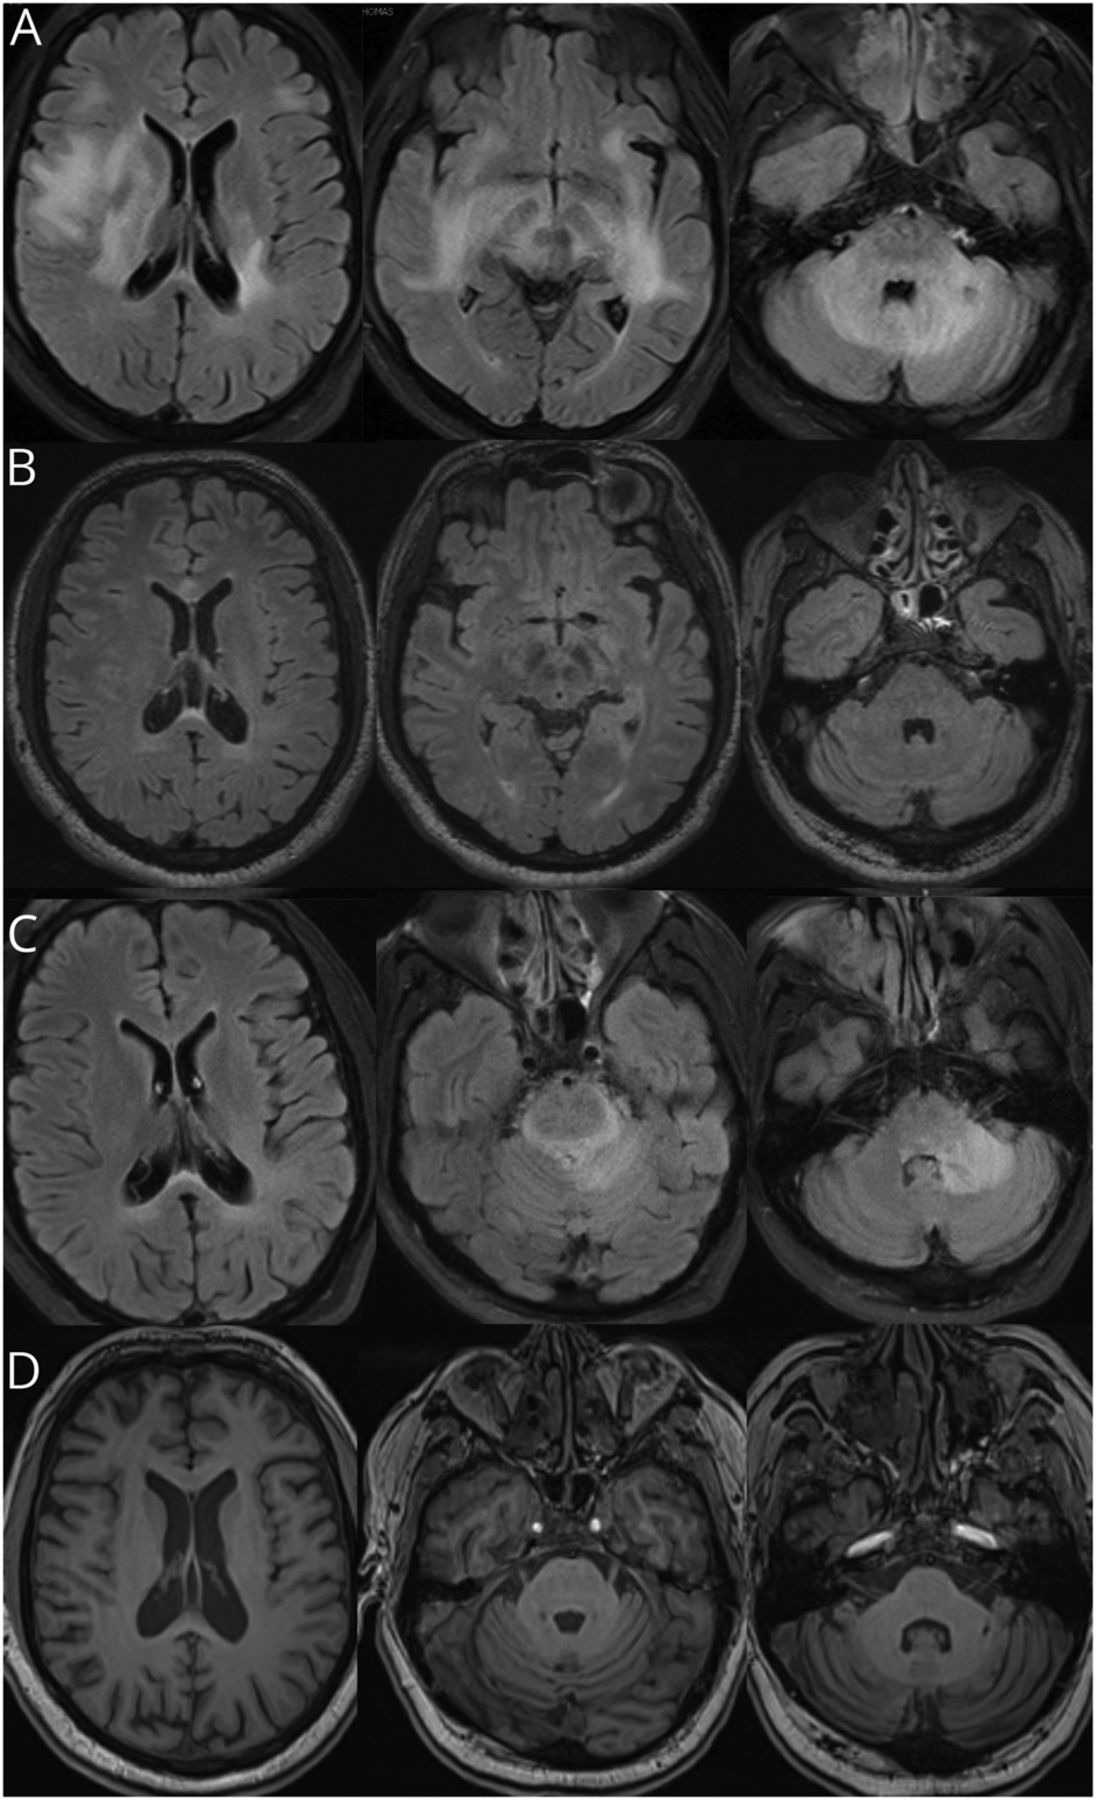

(A)表现出广泛的幕上的和infratentorial白质参与大脑核磁共振T2 /天赋的病人的初始序列复发。(B)复苏从最初的复发。(C)最近3个月后复发和(D)恢复。随时间也明显是发达的脑萎缩(模拟)。

在医院,他的精神状态下降,发达进步的构音障碍和颅神经VI-VIII麻痹导致ICU转移。由于缺乏应对经验治疗,典型的炎症和病毒病因被认为。Arboviral东部马脑炎病毒等感染和Powassan被认为,肠道病毒和疱疹病毒;尽管淋巴细胞性脑脊液细胞增多是更常见的在这些条件下,中性粒细胞可以在疾病早期占主导地位。炎症条件出现嗜中性白血球增多被认为包括neuromyelitis视(NMOSD)遗传病疾病,自身免疫性脑炎的情况并不常见。中枢神经系统血管炎通常呈现淋巴细胞白血球增多,急性脱髓鞘性脑脊髓炎(ADEM)一样,因此被认为不太可能。他表现出显著的临床改善后5天的大剂量甲基强的松龙(IVMP)每天1克,紧随其后的是5天的静脉注射免疫球蛋白(丙种球蛋白),0.4克/公斤/ d。放电时,检查发现残余凝视麻痹。重复MRI显示戏剧性的白质病变的分辨率和对比度增强(图1 b)。

六个月后,他提出与回归热(38.7°C)和改变精神状态。脊髓液这一次是著名的733年的白细胞(淋巴细胞中性粒细胞75%,21%),高蛋白质194.2 mg / dL,正常葡萄糖100 80 mg / dL。革兰氏染色剂、文化和病毒测试呈阴性。核磁共振成像的大脑显示广泛,汇合的T2 /天赋白质hyperintensities增强双边和不完整的。经验又抗菌素产生没有临床反应。考虑到周期性发热和中性白血球增多,对非典型感染,如支原体肺炎、结核分枝杆菌,Q热病或单核细胞增多性李斯特氏菌。这些结果均呈阴性。他收到的第二个课程IVMP,其次是丙种球蛋白的以前的响应。他再一次证明了显著改善,在数周内回到工作岗位。再次重复MRI显示几乎完全解决白质病变。

在接下来的6个月,他说进步认知症状和接受门诊检查包括CSF分析、显示7的白细胞(87%的淋巴细胞,单核细胞13%),蛋白质38.0 mg / dL,葡萄糖100 66 mg / dL。免疫球蛋白g指数为0.46 mg / dL(正常0.0 - -0.7 mg / dL)寡克隆乐队(时常)没有发现,和传染性研究都是负面的。CSF分析的时候,他说一个URI。五天后,他表现为头痛和共济失调。MRI显示一个新的T2 /天赋在左侧小脑半球病变相关的对比度增强(图1 c)。CSF有1750的白细胞(91%的中性粒细胞,4%的淋巴细胞,单核细胞5%),蛋白质248.8 mg / dL,葡萄糖100 62 mg / dL。免疫球蛋白g指数1.16 mg / dL,没有油断路器。革兰氏染色剂、文化和传染病和自体免疫抗体面板是负面的。宏基因组测试后没有产生非典型传染性生物体的证据,和真菌和分枝杆菌培养结果为阴性。

他最近复发后,我们的病人开始anakinra,受体拮抗剂,块IL-1β的活动及IL-1α。2补充诱发IL-1β分泌通过NLRP-1 inflammasome,3和抑制IL-1β改善着促炎细胞因子的影响。此外,IL-1β抑制可能缓慢补充生产和膜攻击复杂(MAC)的形成,限制了进一步补充诱发炎症。4anakinra开始以来,他一直在临床和放射学复发免费20个月。顺序核磁共振脑成像显示萎缩,可能复发性炎症的结果模拟(图1)。其他治疗注意事项包括补充与eculizumab抑制。